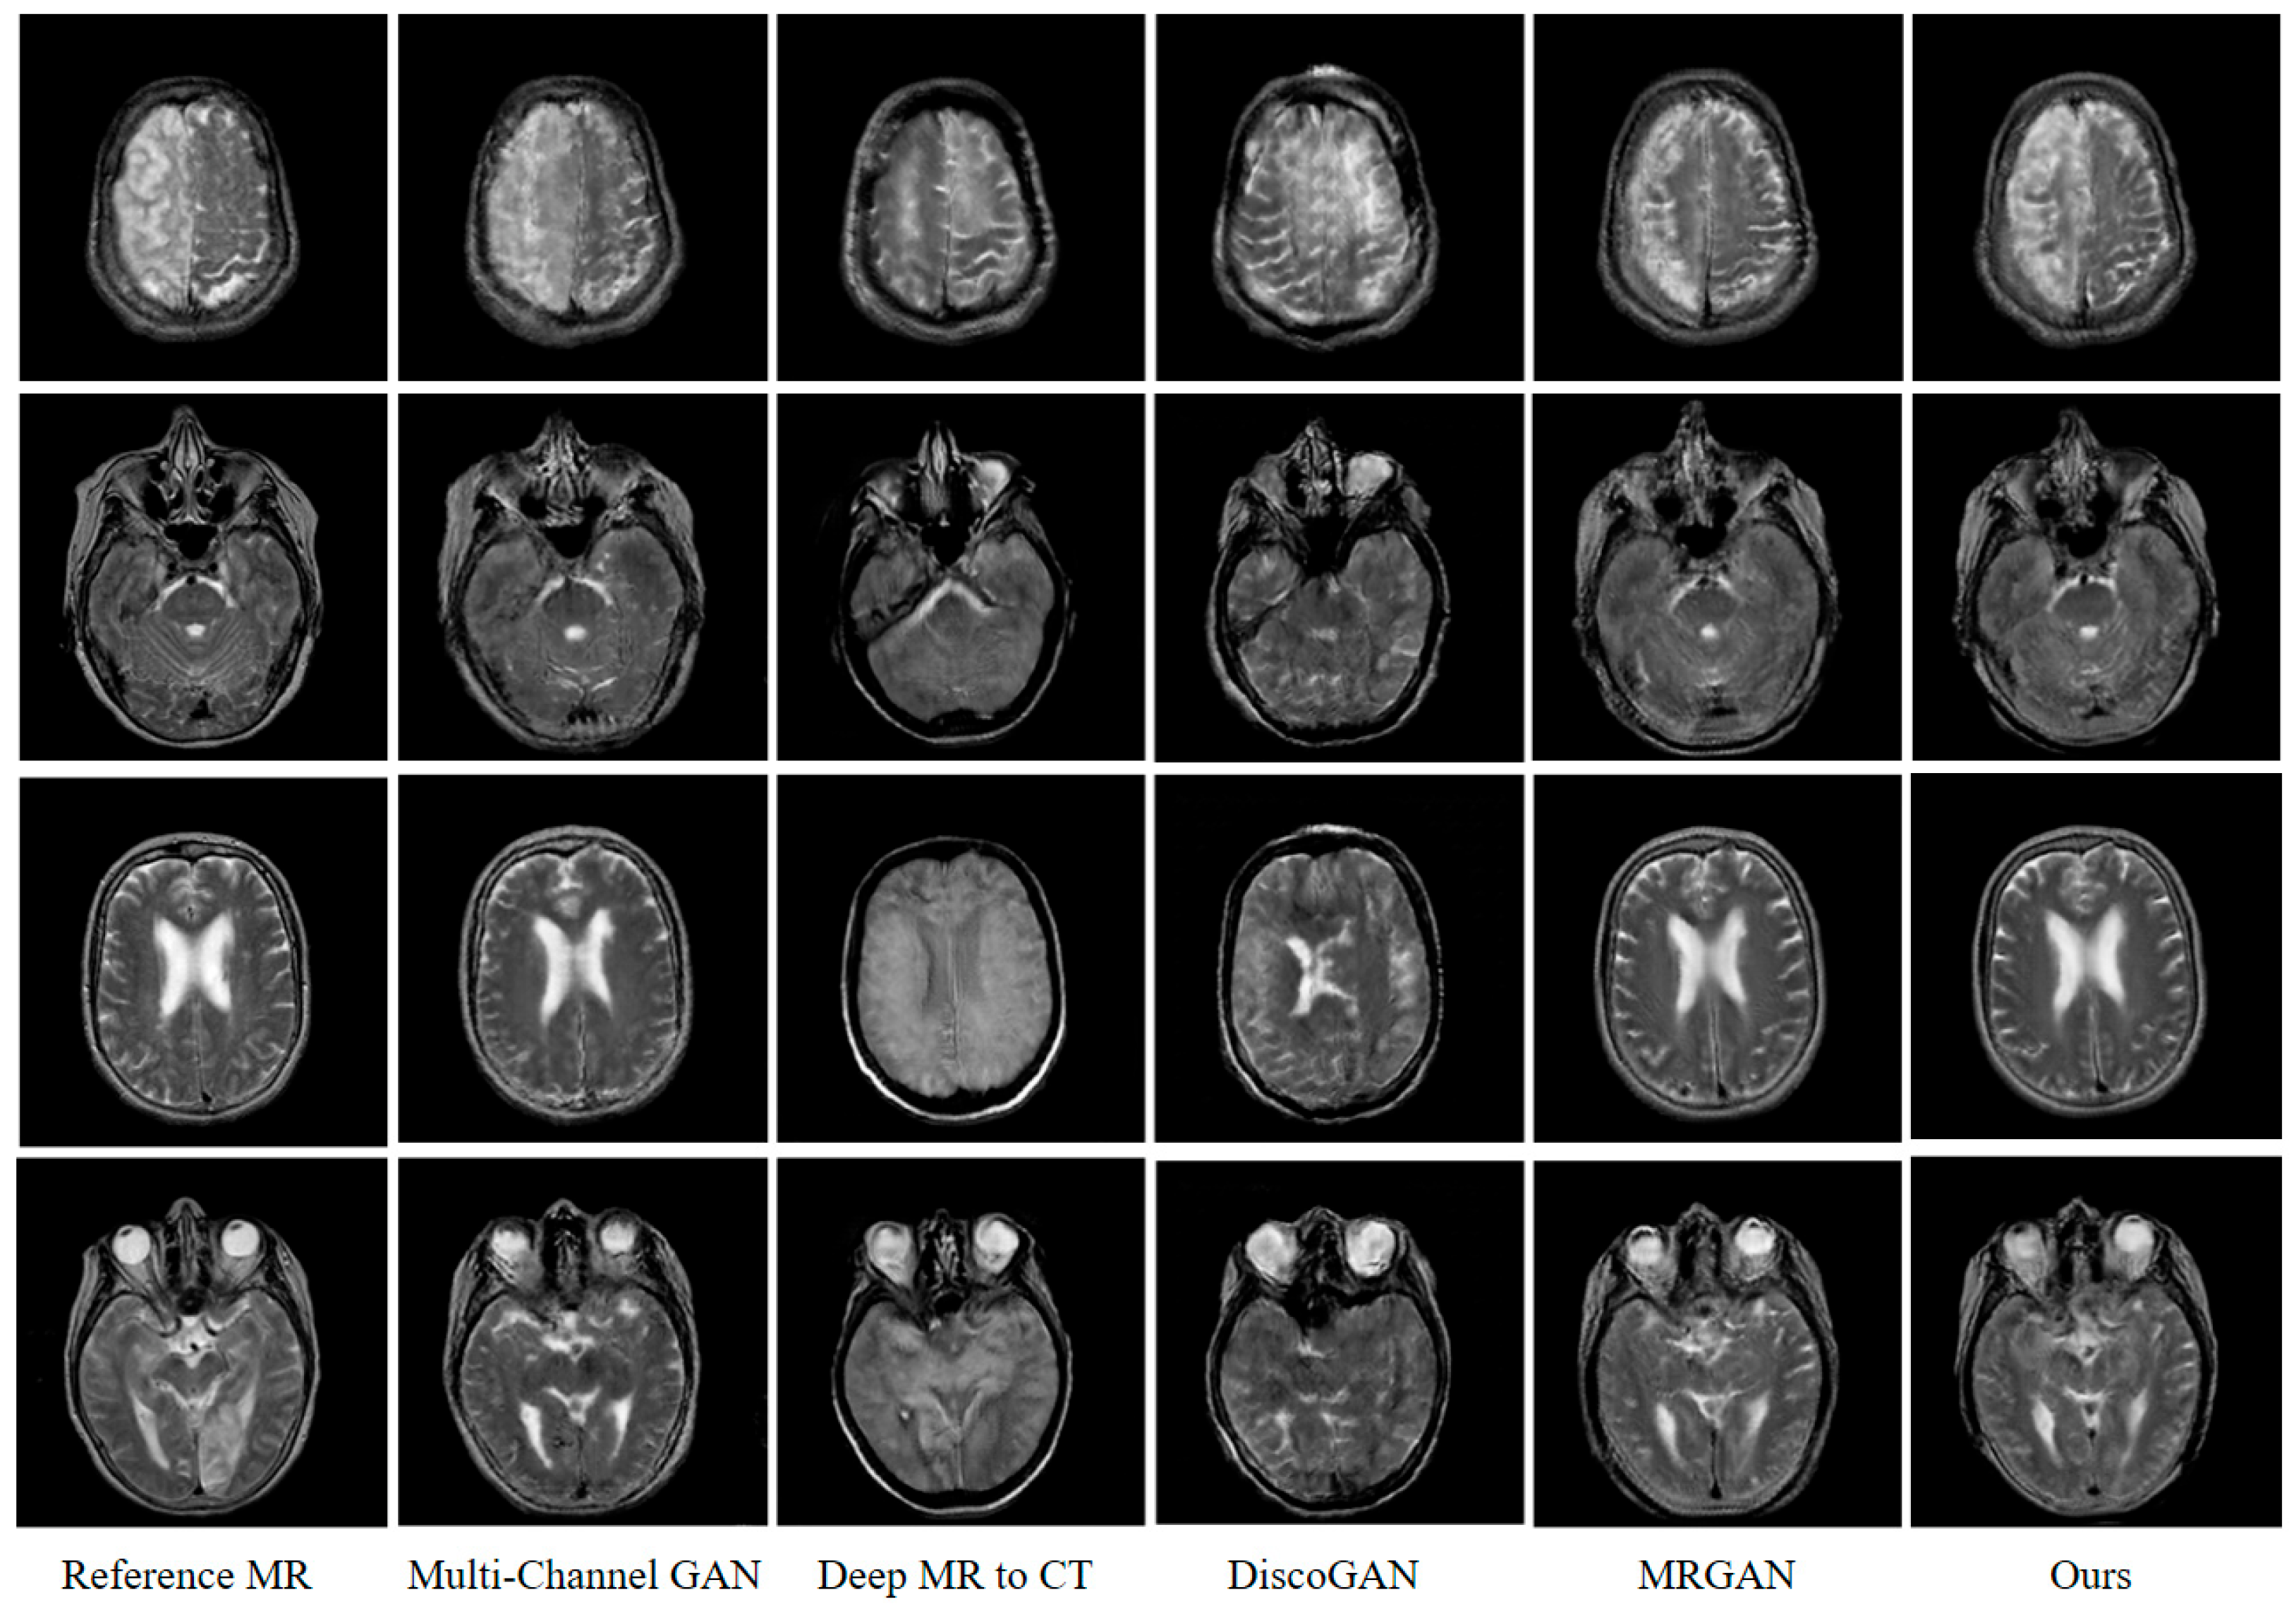

4.3. Comparison of Results under Different GAN Models

| MAE ↓ | RMSE ↓ | PSNR ↑ | SSIM ↑ | PCC ↑ | Imaging Rate | |

|---|---|---|---|---|---|---|

| Multi-Channel GAN | 23.513 | 26.647 | 68.076 | 0.637 | 0.862 | 25.74 ms |

| Deep MR-to-CT | 21.362 | 40.941 | 64.063 | 0.51 | 0.697 | 51.47 ms |

| DiscoGAN | 19.245 | 37.143 | 64.932 | 0.511 | 0.741 | 22.81 ms |

| MR-GAN | 13.293 | 26.061 | 68.312 | 0.642 | 0.868 | 54.38 ms |

| Ours | 12.981 | 25.532 | 68.519 | 0.652 | 0.872 | 70.51 ms |